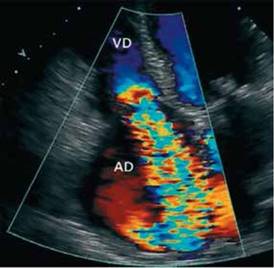

La evaluación debe incluir información sobre las dimensiones de la AD, VD y función sistólica (volumen y fracción de eyección) del ventrículo derecho. Se recomienda la medición de los volúmenes indexados a la superficie corporal, el rango normal de volumen por ETT bidimensional es de 25 ± 7 ml/ m2 en varones y de 21 ± 6 ml en mujeres. Igualmente es importante medir la dimensión del anillo, su dilatación es significativa cuando el diámetro diastólico es mayor o semejante a 40 mm o mayor mm/m2. En la Figura 2 se observa ecocardiograma con regurgitación tricúspide grave.

Eco 3 - D: Insuficiencia tricuspídea grave. Tomado de Flores E. Rev Chil Cardiol 2009; 28:115 - 119.

Figura 2: ECOCARDIOGRAFÍA TRICUSPÍDEA

Se reitera que este método complementario, necesariamente debe valorar la función ventricular derecha, cuantificar la severidad de la regurgitación, la dilatación del anillo y el modo de coaptación de las valvas incluyendo el aumento del tethering (desplazamiento apical de las valvas tricúspideas), sabiendo que una diferencia de este desplazamiento mayor a 8 mm o un área de tenting sistólico mayor a 1.0 cm2 se asocia con IT severa4,5.